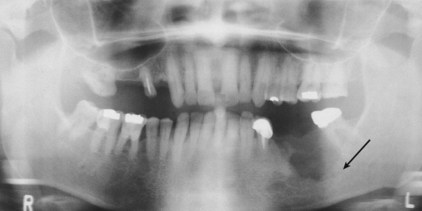

• A panoramic view of the mandible (an orthopantomogram):

• Is helpful to assess the general architecture of the mandible in relation to the dento-alveolar structures and invasion by the tumor (Figure)

• However, for technical reasons:

• The midline of the mandible near the symphysis is not adequately evaluated by a panoramic view

• In addition, early invasion of the lingual cortex of the mandible is not seen on a panoramic view